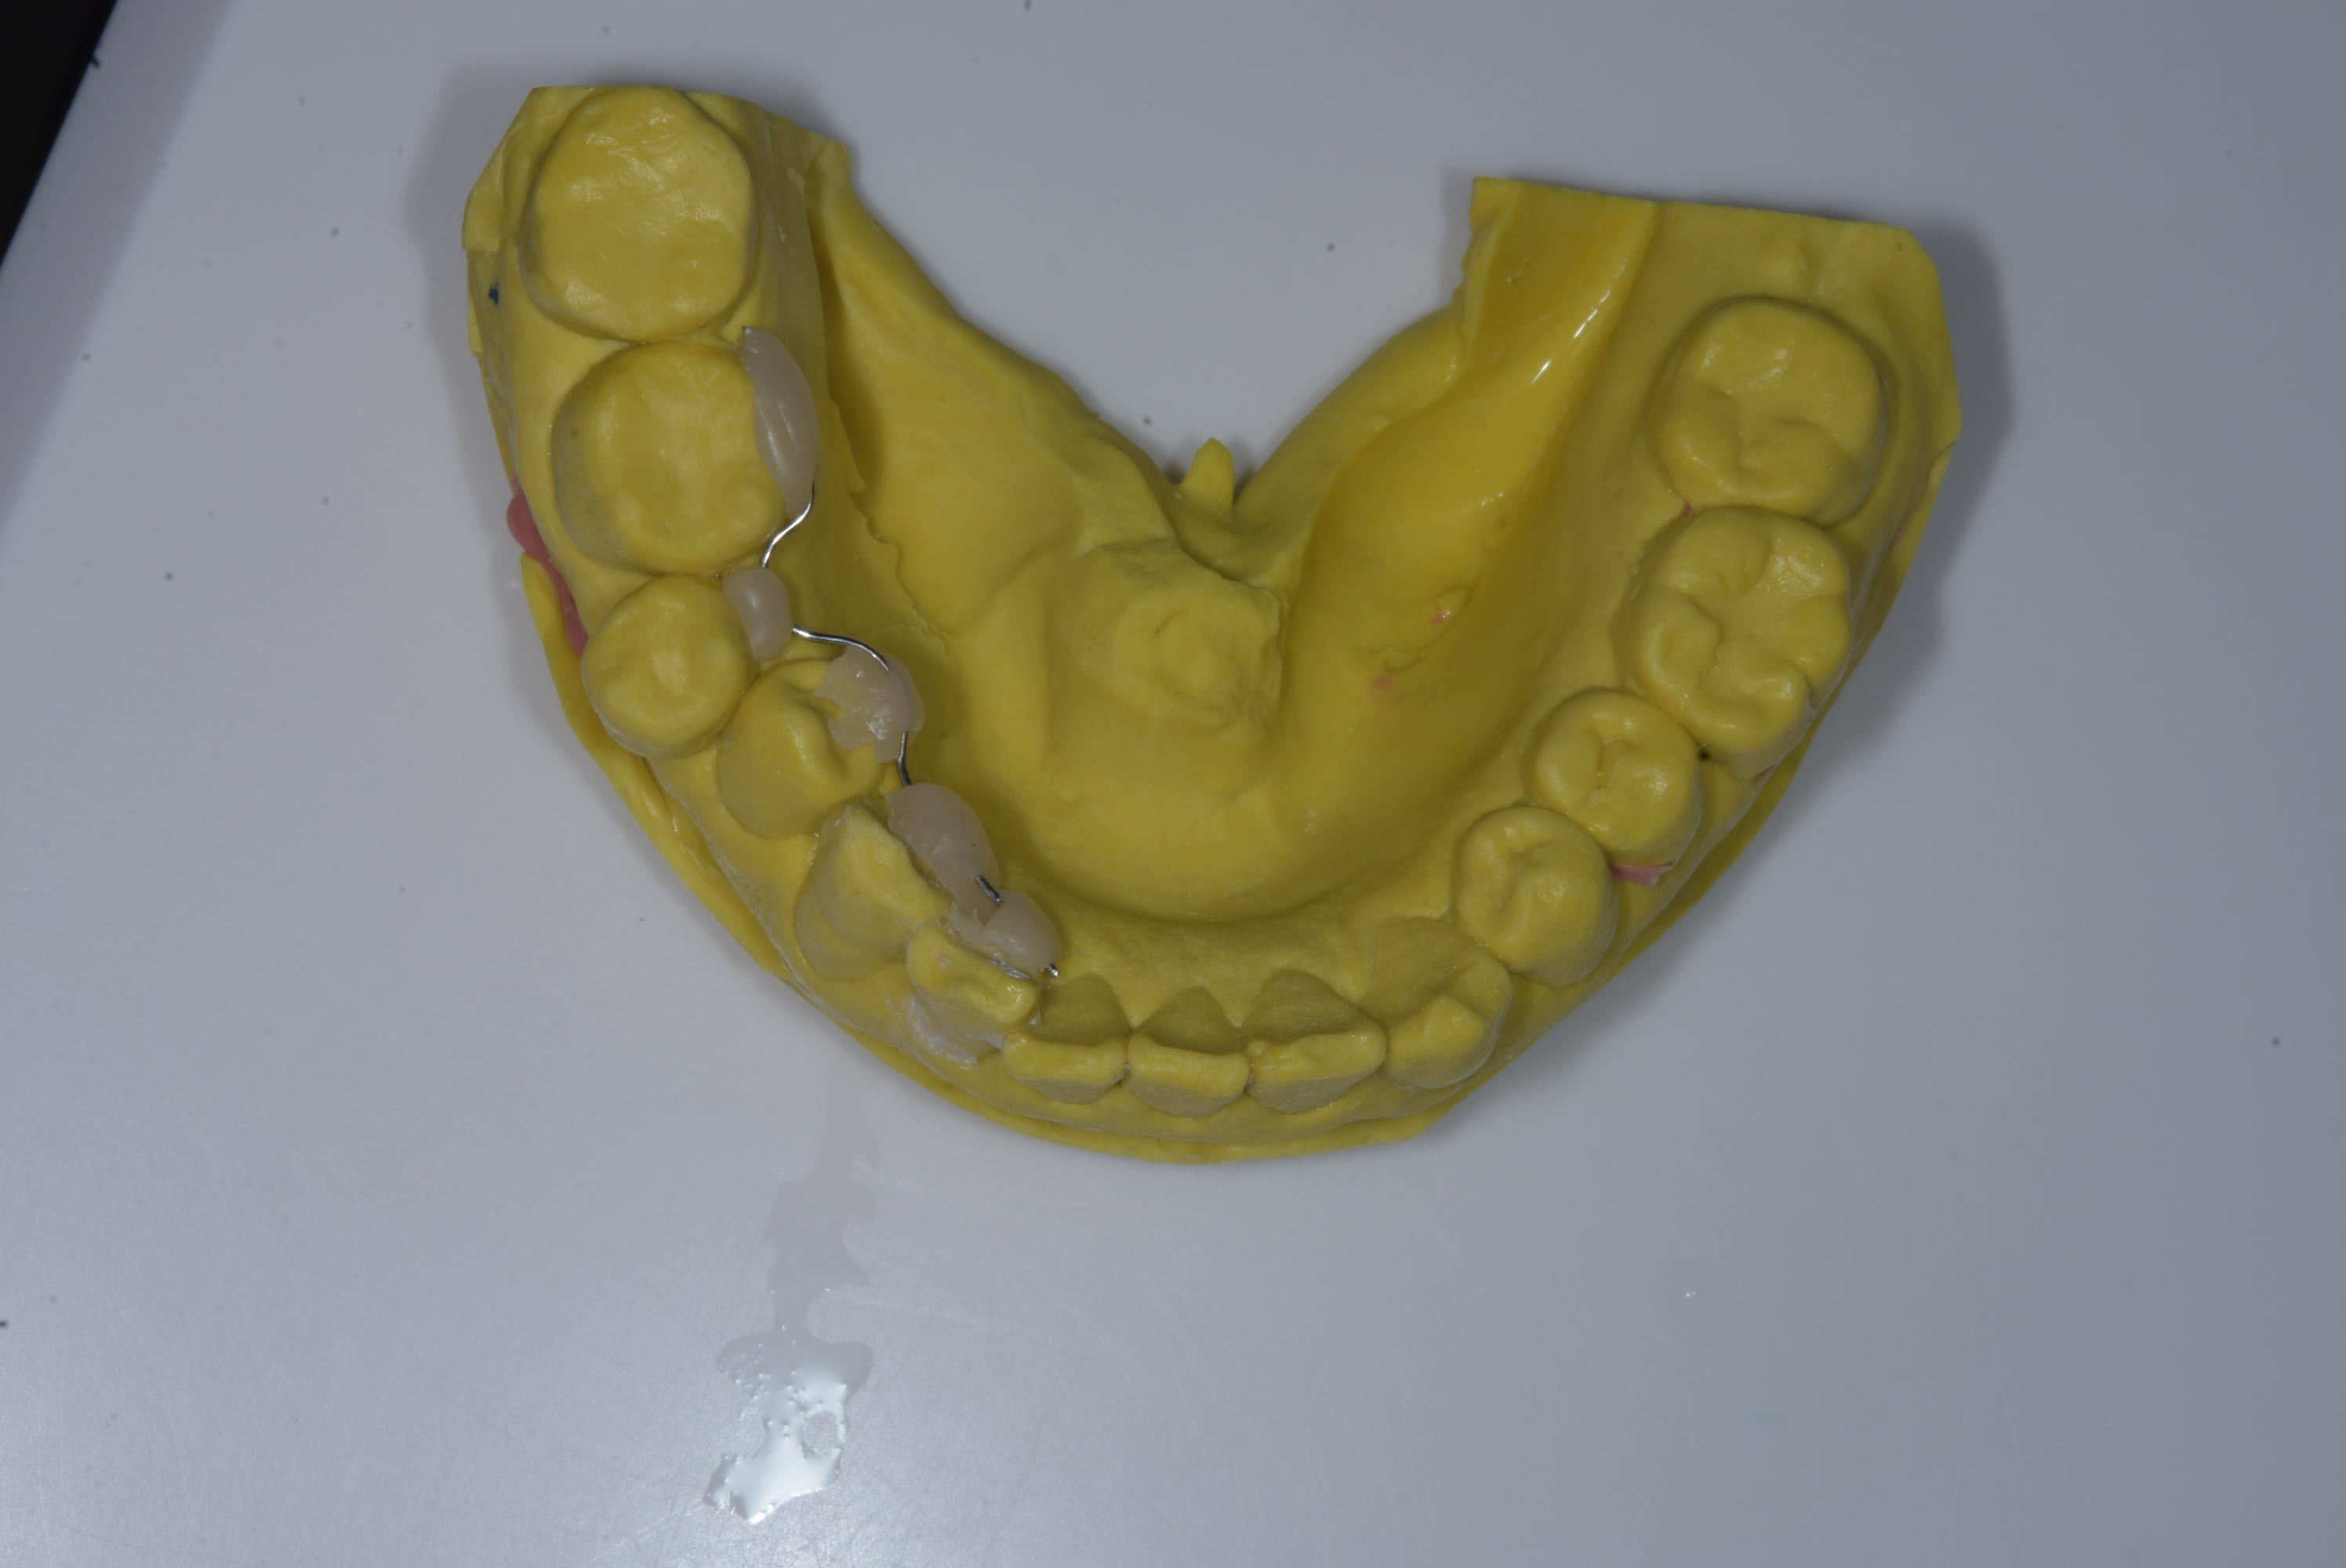

Pourquoi dans ce deuxieme cas vous collez 35/45 , alors qu'au premier cas vous colliez 34 ?

Y-a-t-il un interet particulier ?

Sur le premier cas la 47 présenter une rotation initiallement et j'ai collés la 45 pour avoir plus d'amplitude.

En résumer:

Plus d'emplitude peut permettre de mettre un fil de diamétre plus important, plus rapidement. Ca permet aussi de mettre un ressort plus long donc avec un temps d'activation plus long. Par contre le fil est plus long donc c'est potentiellement moins confortable pour le patient.

Si possible j'essais de maximiser le confort vue que c'est le point important avec une patientel adultes.